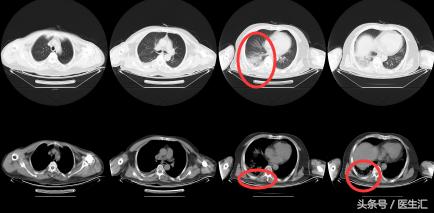

【 胸部 CT】2016.10.05

结果示:

本病例表现很普通,在临床上经常会碰到这种类型的,拿到这个病例首先可能会考虑是肺炎,但是真的是肺炎吗?为了明确诊断,再次详细问了患者的病史,下面来看看患者的病史特点,然后进行分析:

因为发现患者1 个月前有外伤手术史,那么是否可能有其他可能?所以我们给患者做了一个CTPA。